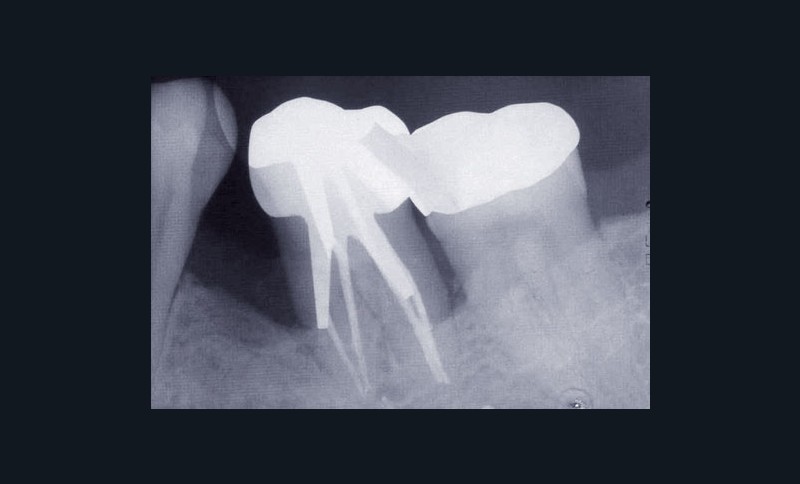

Les examens cliniques et radiographiques montrent une parodontite chronique généralisée (fig. 1a à m).

Nous décidons d’entreprendre une thérapeutique initiale parodontale classique dans tous les secteurs, y compris l’extraction de 24, un bridge de 45 à 48 avec 46 en pontique, un bridge complet de contention de 17 à 27 sur 11 piliers dentaires et une greffe épithélio-conjonctive sur 31. Cette dernière ne sera jamais réalisée. Le bridge maxillaire permettra de réduire le surplomb antérieur et d’améliorer le sourire de la patiente, ce qui constitue l’une de ses demandes.